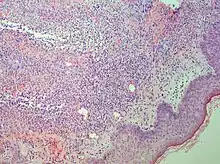

| Generally/Not otherwise specified | Typical findings, called "vacuolar interface dermatitis":[6]

|

![]() |

An interface dermatitis with vacuolar alteration, not otherwise specified, may be caused by viral exanthems, phototoxic dermatitis, acute radiation dermatitis, erythema dyschromicum perstans, lupus erythematosus and dermatomyositis.[2]